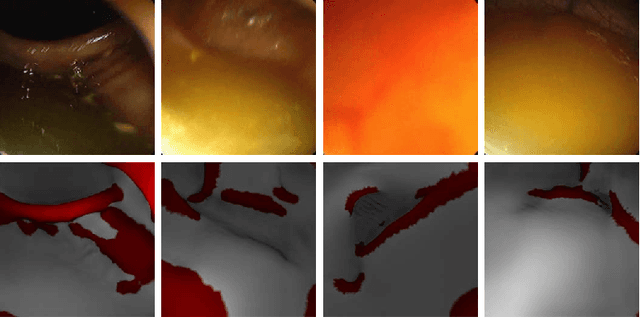

Haustral folds are colon wall protrusions implicated for high polyp miss rate during optical colonoscopy procedures. If segmented accurately, haustral folds can allow for better estimation of missed surface and can also serve as valuable landmarks for registering pre-treatment virtual (CT) and optical colonoscopies, to guide navigation towards the anomalies found in pre-treatment scans. We present a novel generative adversarial network, FoldIt, for feature-consistent image translation of optical colonoscopy videos to virtual colonoscopy renderings with haustral fold overlays. A new transitive loss is introduced in order to leverage ground truth information between haustral fold annotations and virtual colonoscopy renderings. We demonstrate the effectiveness of our model on real challenging optical colonoscopy videos as well as on textured virtual colonoscopy videos with clinician-verified haustral fold annotations. All code and scripts to reproduce the experiments of this paper will be made available via our Computational Endoscopy Platform at https://github.com/nadeemlab/CEP.